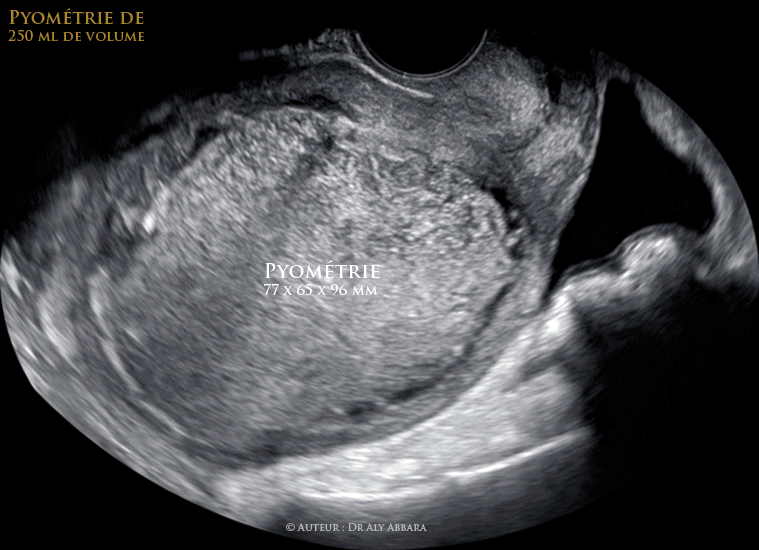

Utérus : volumineuse pyométrie de 250 ml de volume

Utérus : volumineuse pyométrie de 250 ml de volume.

Les parois de l'utérus sont amincies sous la pression du contenu utérin ; aucune lésion végétante endo-utérine n'a été mise en évidence.

La pression exercée sur la paroi antérieure de l'utérus à l'aide de la sonde endovaginale permettait de créer des mouvements de déplacement et de tourbillonnement des particules composant ce contenu utérin.

Cliniquement cette pathologie se manifestait par des douleurs pelviennes évoluant depuis une semaine et de la fièvre depuis quelques heures, avec biologiquement une hyperleucocytose et un taux de CRP (protéine réactive C) à 330 mg/l.

• La patiente est âgée de 59 ans, ménopausée depuis l'âge de 45 ans ; atteinte d'un diabète type II, négligé et non pris en charge depuis plusieurs années (glycémie à jeun est à 3,1 g/l).

• Cette pyométrie a été drainée par voie vaginale en dilatant l'orifice interne du col utérin : évacuation d'environ 250 cc d'une collection endo-utérine purulente ; il s'agit d'un pus jaune grisâtre très malodorant (sentant le soufre).